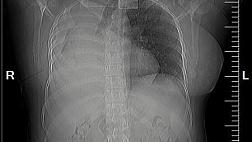

Пациентка переведена к нам в отделение торакальной хирургии из родильного отделения. Будучи беременной на 9 месяце COVID-19 с возникновением двухсторонней вирусно-бактериальной пневмонии с деструкцией в нижней доле правого легкого, эмпиемой плевры и бронхоплевральным свищем. По данным Р-КТ органов грудной клетки: полость деструкции в нижней доле правого легкого. Выполнено дренирование плевральной полости справа. У пациентки – утечка воздуха по дренажу из плевральной полости. 05.06.2020 выполнена клапанная бронхоблокация промежуточного бронха (блокатор Medlung №12) с хорошим клиническим эффектом (сброс воздуха по прекратился через 6 часов после вмешательства). Но, через 2 дня пациентка откашляла блоктор.